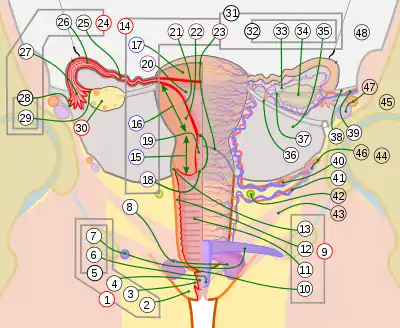

Additional images

14. Uterus: Parts: 15. Cervix; 16. Body and 17. Fundus. 18. Orifices: External and Internal; 19. Cervical canal; 20. Uterine cavity; Layers: 21. Endometrium; 22. Myometrium and 23. Perimetrium

24. Fallopian tube

30. Ovary

31. Visceral pelvic peritoneum: 32. Broad ligament (with 35. Mesometrium)

Ligaments: 36. Round

Blood vessels: 40. Uterine artery and veins

Other: 42. Ureter; 46. Internal iliac vessels (anterior branches); 48. Abdominal cavity